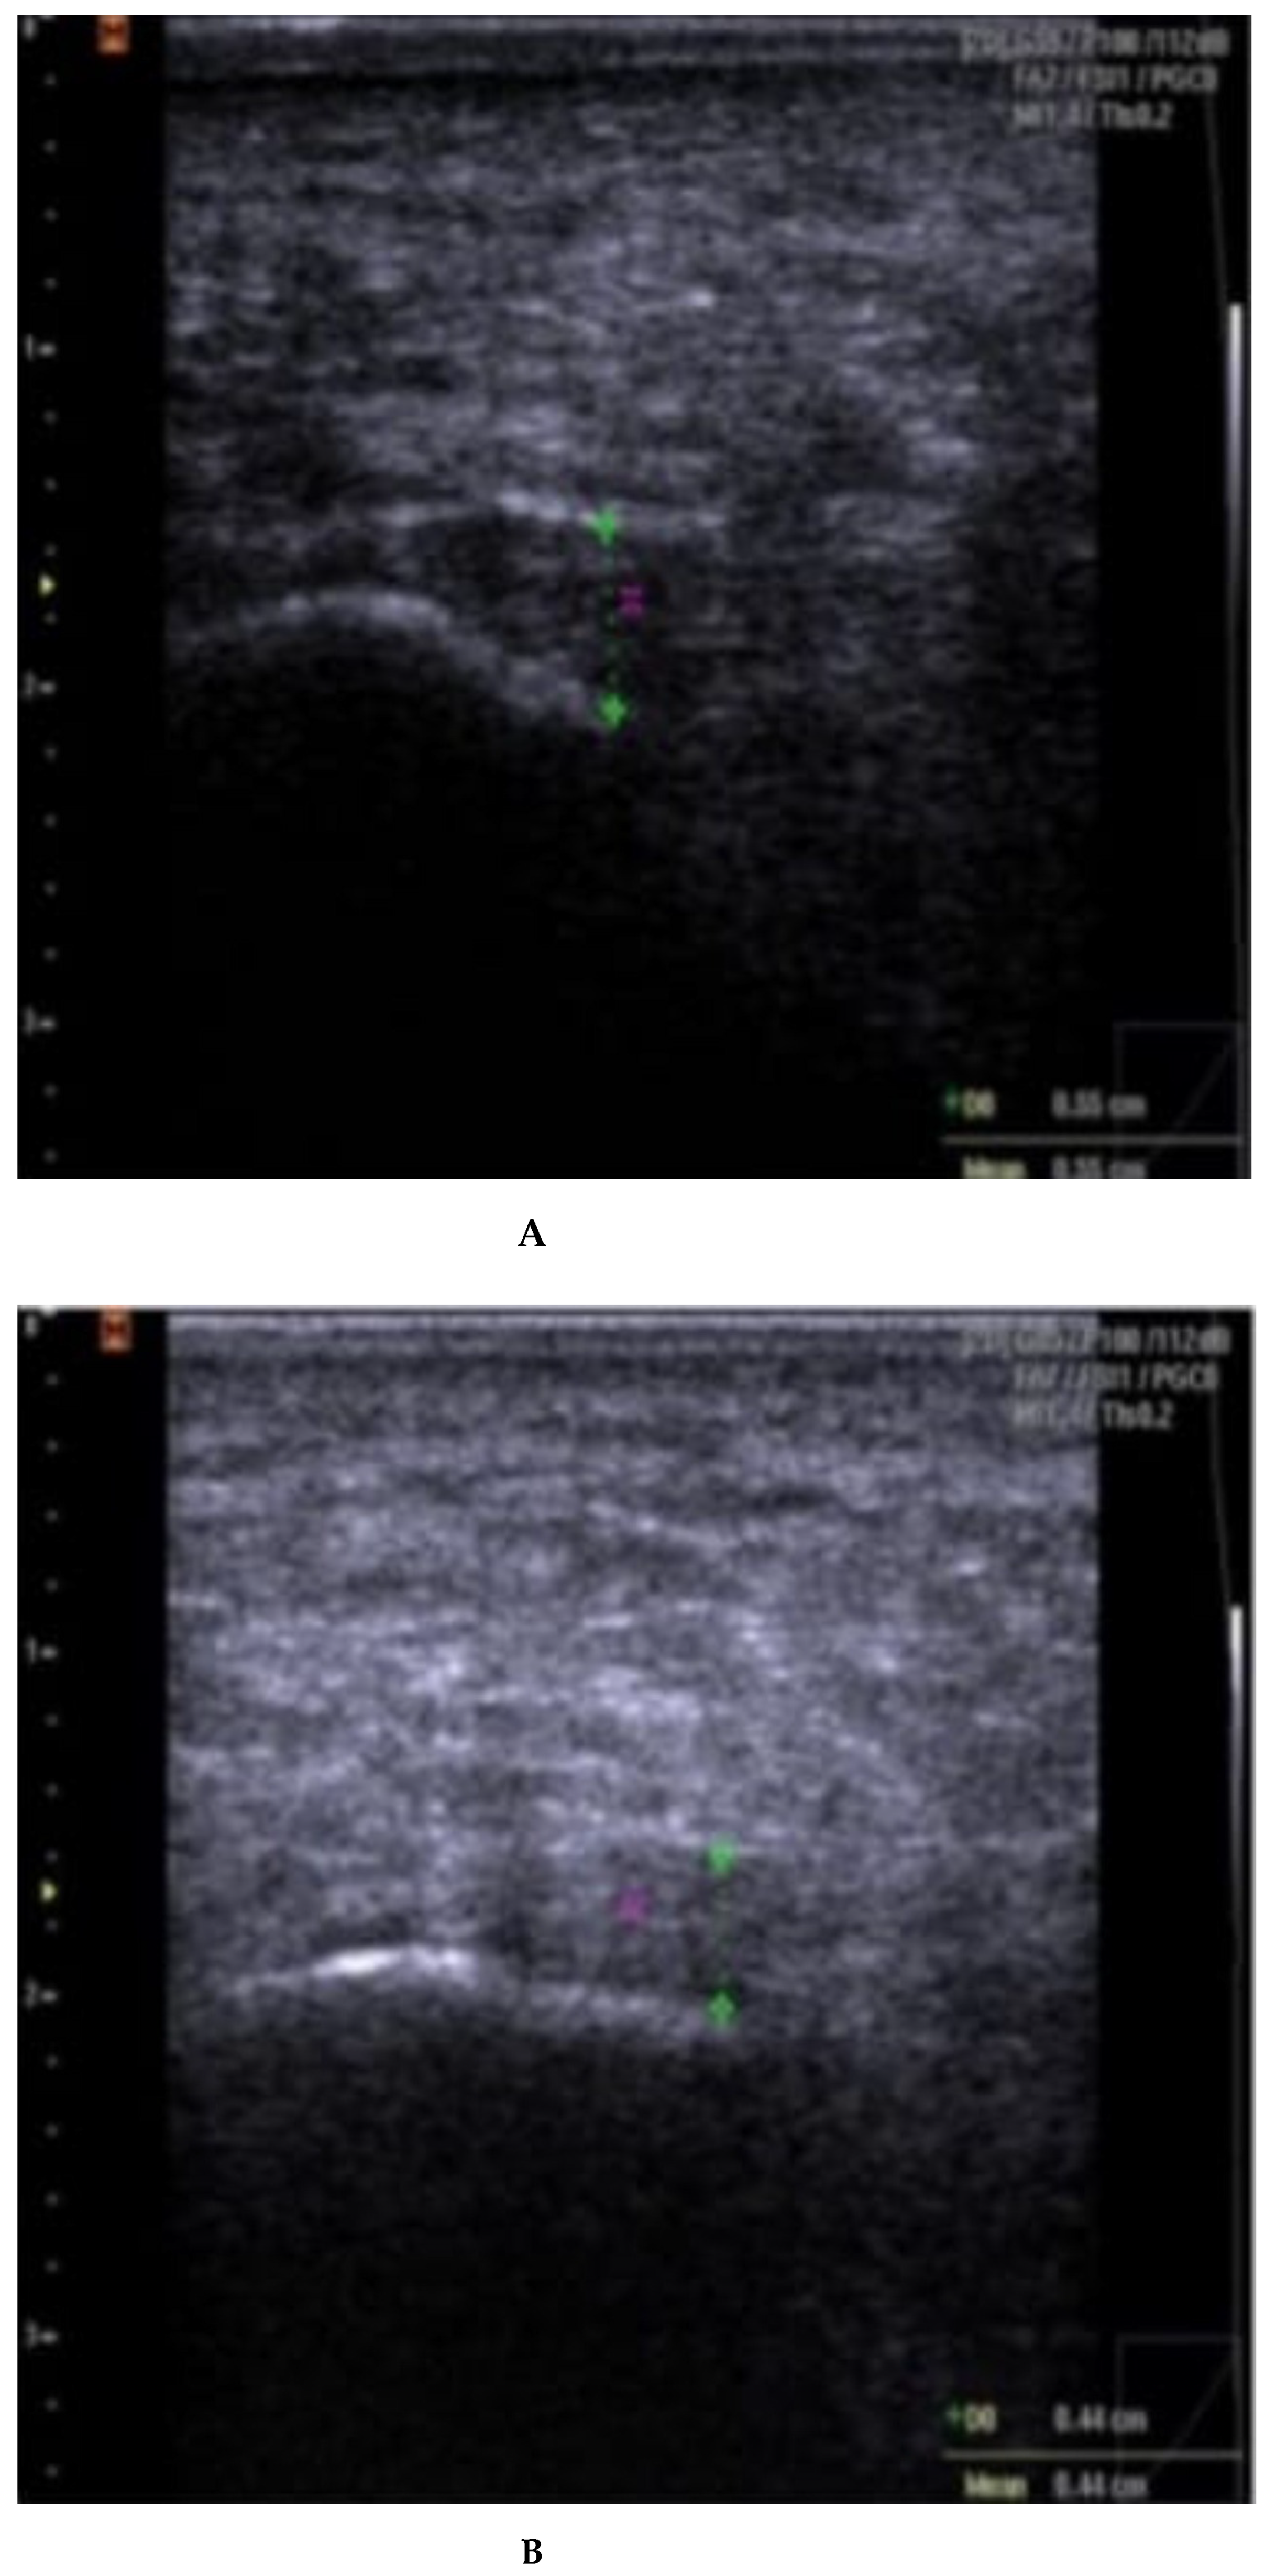

Fascia thickness and echogenicity. All patients had an increased plantar fascia thickness (3.50–8.0 mm) at baseline when measured with MSKUS, and all had hypo-echogenicity. There was a significant difference in the reduction of the plantar fascia thickness between the two groups at 4 weeks follow-up in favor of CSI + TUS (p = 0.004, Table 5), as also shown in Figure A1 and demonstrated in ultrasound images in Figure A2 and Figure A3. At the 12-week follow-up, plantar fascia thickness was significantly higher in the CSI + TUS group (p = 0.012), with an insignificant difference in the decrease between both groups (p = 0.216).

Echogenicity change (Figure A2 and Figure A3) from hypoechoic to iso- or hyperechoic was statistically significant in both groups at 12-week follow-up, but no significant difference was found between the groups (p = 0.208; Table A1).

(A–C): plantar fascia thickness and echogenicity before, after 4 weeks, and 12 weeks follow-up (CSI followed by therapeutic US). (A). Plantar fascia thickness (0.55 cm) and echogenicity (hypoechoic) before CSI injection followed by therapeutic US; Ankles in 90° dorsiflexion; Images obtained just medial to the midline, at the proximal end of the plantar fascia, distal to its origin, from the medial tubercle of the calcaneus; Thickness of the plantar fascia was measured from the base of the medial calcaneal tubercle, where a bright echogenic line was easily visible. (B). Plantar fascia thickness (0.44 cm) and echogenicity (hypoechoic) after 4 weeks. (C). Plantar fascia thickness (0.41 cm) and echogenicity (hypoechoic) after 12 weeks.